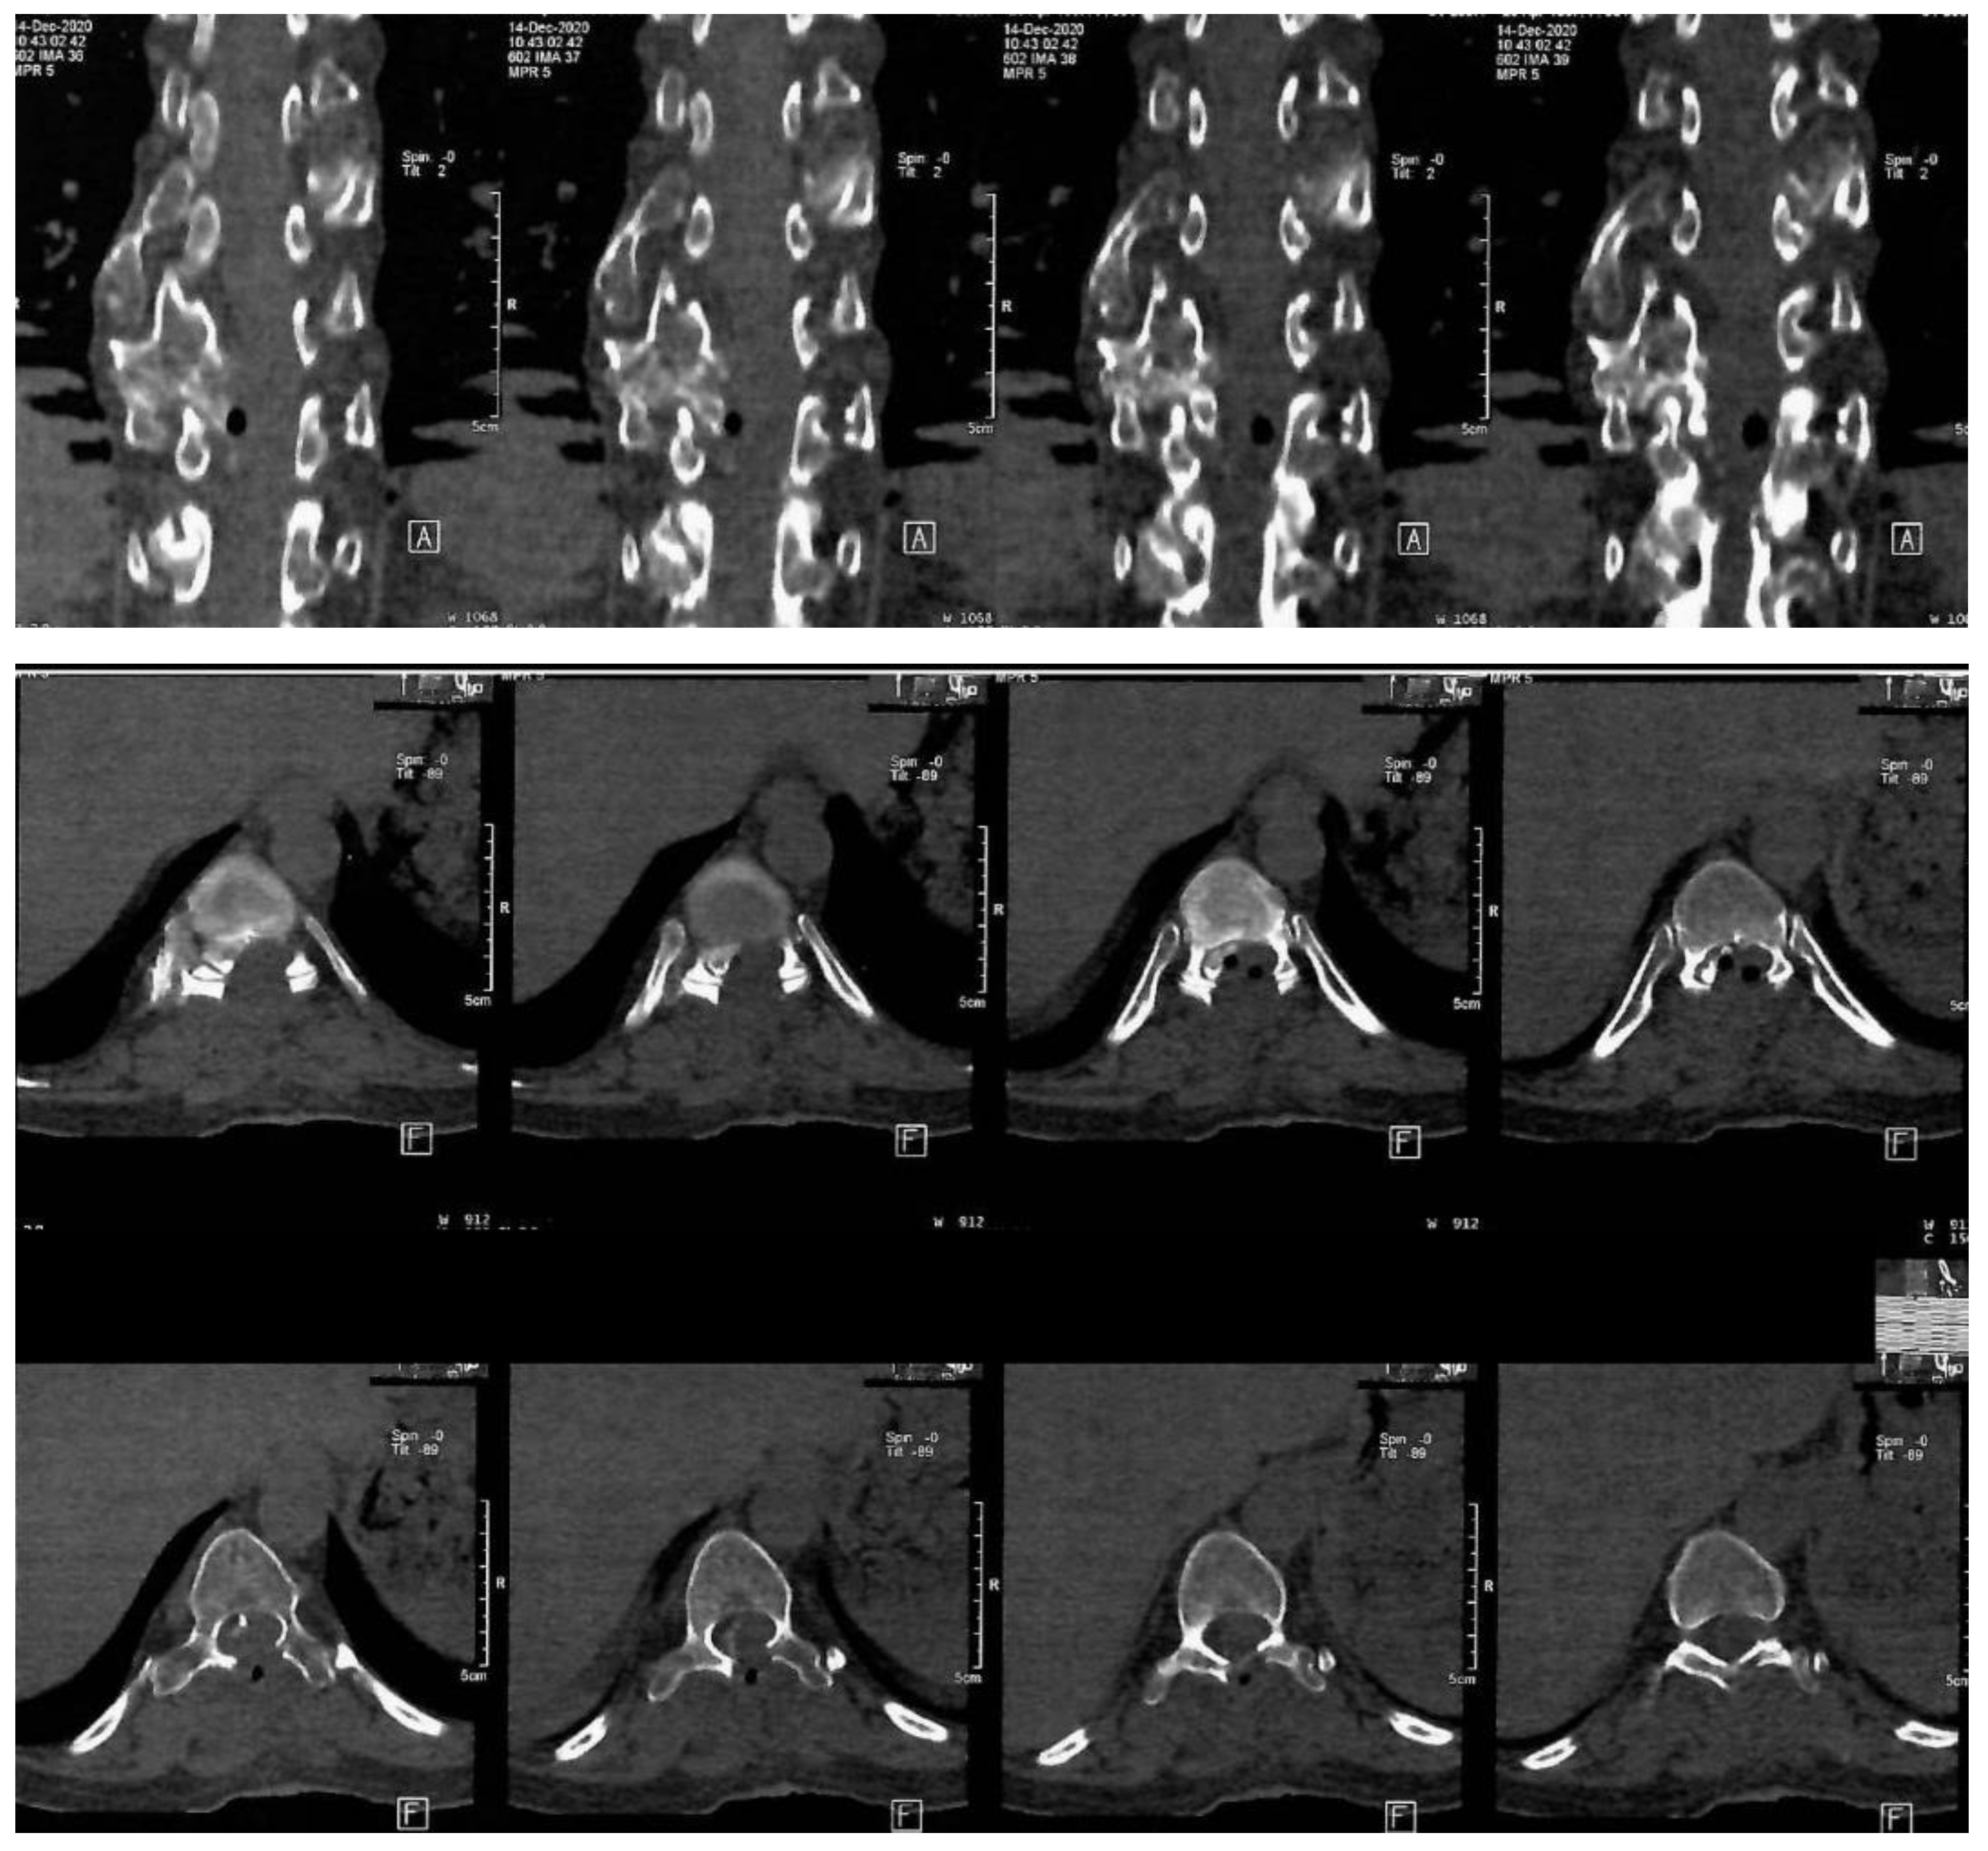

The mass was sent to histopathology in our clinic. According to the report, fragments of osteochondroma were discovered, which was compatible with HME. The operation was a great success, with a considerable improvement of the neurological status. The Frankel D paraparesis remitted in about a week. A CT scan was performed 6 days after surgery. The Frankel D type is characterized by the preservation of some degree of motor function below the level of the spinal cord injury, allowing the patient to have active movement, although it may not be sufficient to support all activities of daily living independently. Sensory function is also preserved to some extent below the level of the injury, enabling the patient to feel touch and other sensations, although the sensitivity may be reduced. Patients with Frankel D can usually walk, but they may require assistance or aids such as braces, crutches, or walkers, as their muscle strength is often not sufficient to support full, unassisted mobility. Note the important enhancement of the spinal column bio-architecture, plus the increase in the vertebral canal width (Figure 3).

Figure 3. Postoperative thoraco-lumbar native CT scan. A: indicate the anterior (front) side of the body relative to the position of the cross-sectional slices being viewed, F: indicates the orientation of the patient’s feet during the scan.

The postoperative thoracal CT scan showed visible laminectomy, with marked enlargement of the vertebral canal caliber. The postoperative CT scan confirmed the total resection of the osteochondroma.